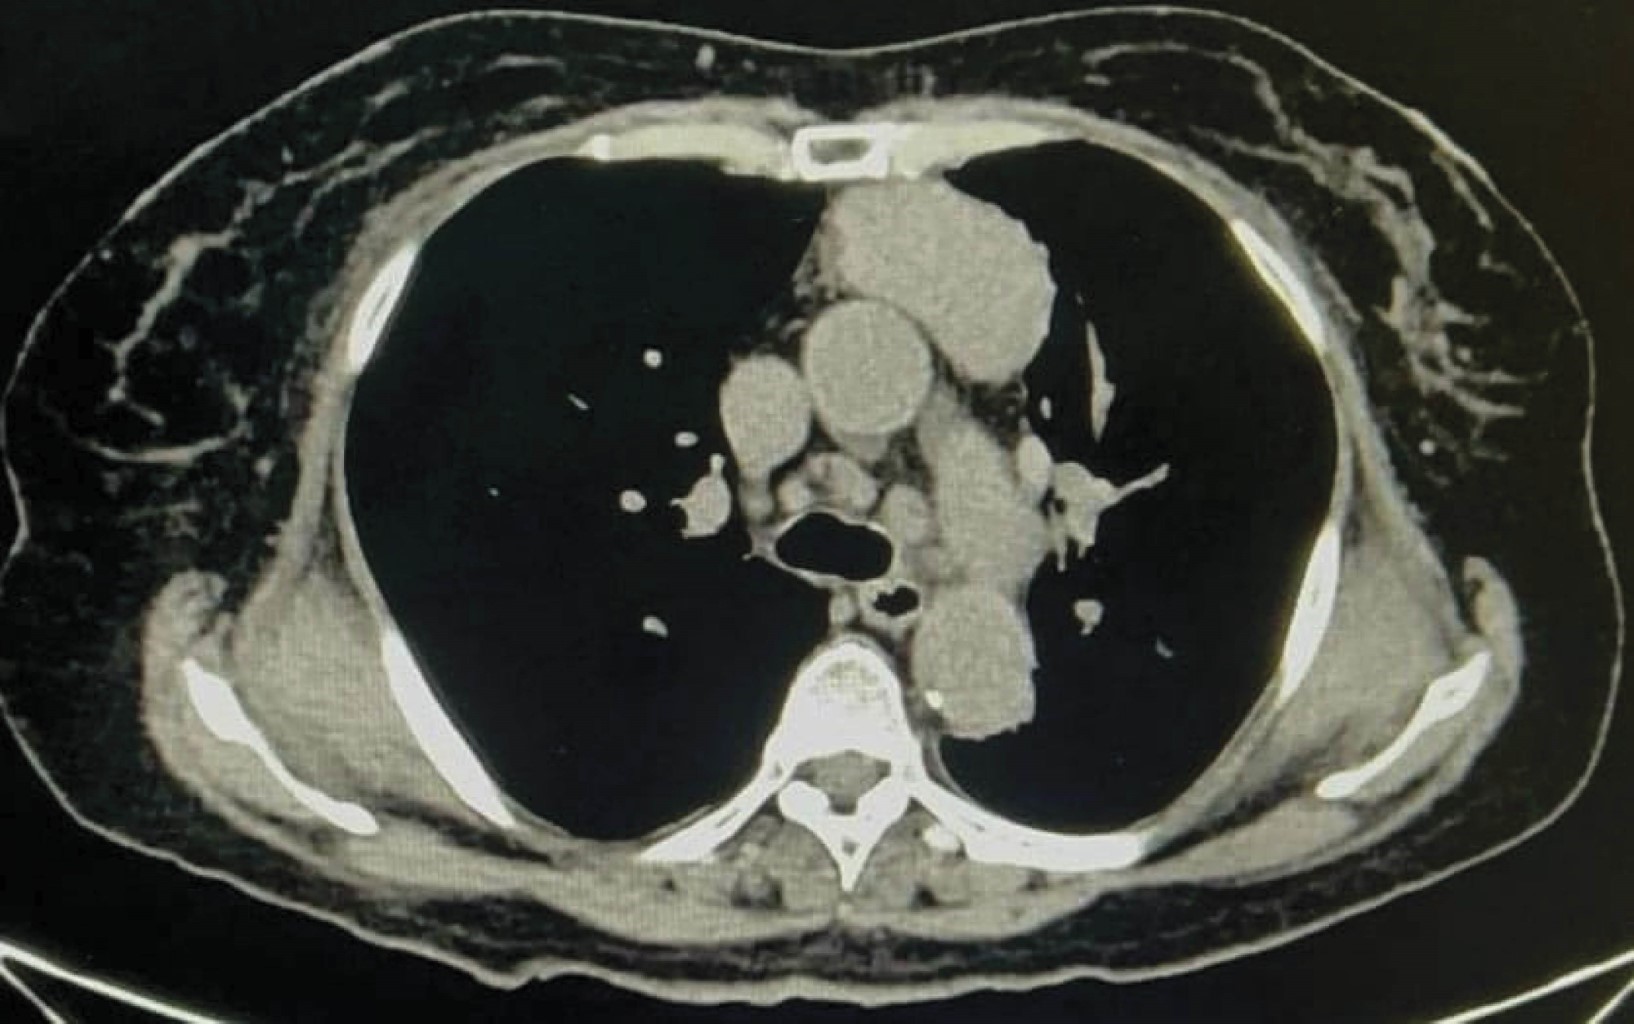

Timoma tipo A resecado quirúrgicamente mediante timectomía de mínima invasión

El timoma es el tumor mediastínico más común y consiste en una neoplasia de las células epiteliales del timo. Provoca síntomas compresivos locales como efecto de una masa en el cuello. La cirugía es el tratamiento principal. Recientemente, se han propuesto abordajes mínimamente invasivos asistidos por toracoscopia. Estos abordajes se caracterizan por estancias hospitalarias más cortas, bajas tasas de morbilidad y buenos resultados estéticos. Sin embargo, es importante individualizar el mejor tipo de abordaje para cada paciente, destacando la importancia de la resección quirúrgica completa en el manejo de estos tumores.

Figura 1